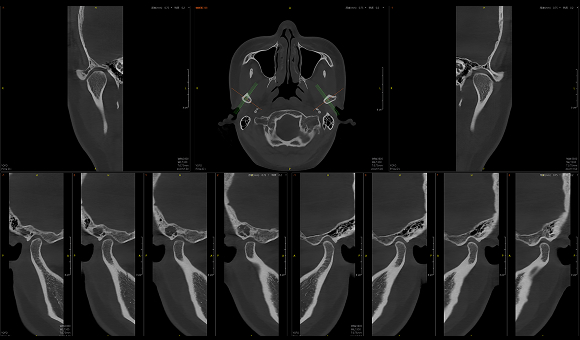

只需一次单圈扫描即可获得CT、3D全景和3D正/侧位影像,并能同时生成3D TMJ视图

提高诊疗效率,避免过度检查,减少患者所受的辐射

• 3D TMJ视图

3D TMJ视图